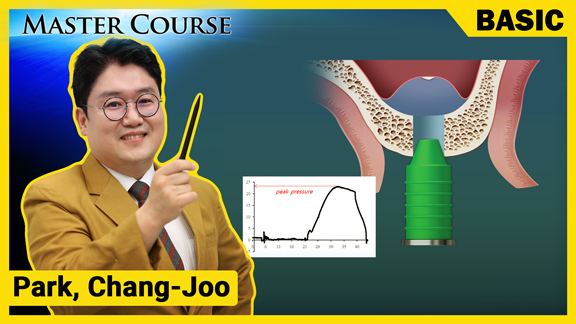

[BASIC] Implant Motor and Surgical KIT

마스터코스

2020-04-13T00:00

[BASIC] Local Anesthesia for Implant Surgery

마스터코스

2020-02-20T00:00